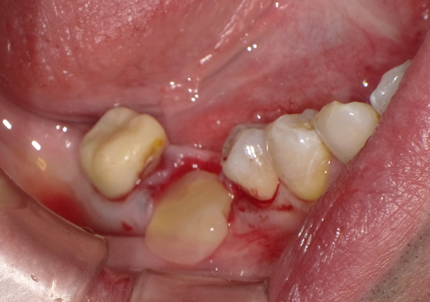

3. 右上1番・左上2番 SST(ソケットシールドテクニック)

【右上1番SST 口蓋側歯根の抜歯】

【右上1番 SST インプラント埋入後に初期固定オステル値の測定】

← 右上1番 SST CT画像

※ CT画像にて歯根片が確認できる

【左上2番 SST 口蓋側歯根の抜歯】

← 左上2番 SST CT画像

4. 右上2番インプラント埋入

埋入後に初期固定35N/cmを確認する

← 右上2番 通常の埋入 CT画像